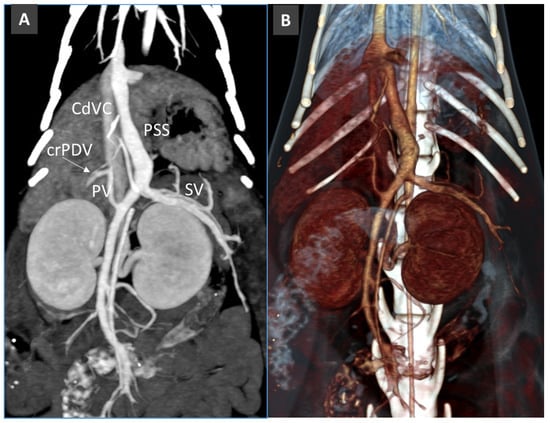

Congenital Portosystemic Shunt

3.7. Acquired Portosystemic Shunts (APSSs)